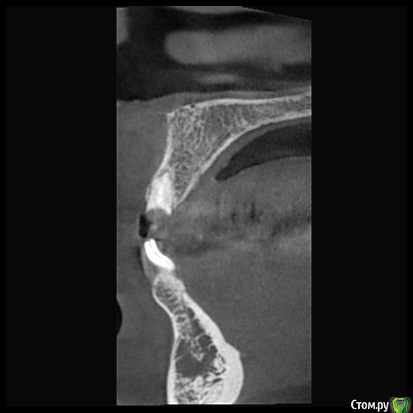

колесников Опубликовано 27 марта, 2018 Поделиться Опубликовано 27 марта, 2018 Так одно из другого выходит,разве нет? Нет винтовой фиксации -значит не верное позиционирование. По мне-так. Цемент,раскручивание тли перелом винта-это уже дополнительные бонусы. Про АД не скажу ,я его косяков не видел (кто-нибудь вообще видео?). С особенностями Нобеля знаком,от этой системы давно отказался, именно из-за особенностей и с АД по этому поводу несколько раз сцеплялся,но каждый остался при своём. Вот свежий случай. Сторонне работа,около 10 лет. Кстати Нобель,но тут не в этом дело. Видно что изначально Имплант поставлены по направлению гребня (где кость была),ортопед угловым все вывел. Итог налицо. Скажете :тут по другому никак,такой гребень. Сейчас работаю в первом секторе,гребень аналогичный,удалось выйти на винтовую и даже с нагрузкой. Ссылка на комментарий

колесников Опубликовано 27 марта, 2018 Поделиться Опубликовано 27 марта, 2018 (изменено) Вот ещё случай (из интернета). Тут ситуация не однозначная,с одной стороны абатмент изначально из диоксида циркония,а с другой это похоже штрауман тл . завтра скину свой случай,у меня мис стоит стандартный абатмент и коронка с розовой десной. Суть примерно такая же. Вестибулярное положение платформы из-за угла положения импланта,лизис компактной пластинки и прогнозируемо рецессия. Видно,что закрывать массированно мягкими тканями не резон,будет шишка. Надо смещаться коронально,но придётся менять форму абатмента и коронки чтобы было где расположится прикреплённой слизистой. Так вот,на платформенном соединении это практически не возможно сделать ,угроза переточить стенку абатмента и получить перелом. Проще переустановить Имплант в другом положении. Но иногда это практически не возможно Изменено 27 марта, 2018 пользователем колесников Ссылка на комментарий

Irouil Опубликовано 28 марта, 2018 Поделиться Опубликовано 28 марта, 2018 Имхо в первом случае просто установлен толстый имплантат в тонкий гребень. К тому же там было куда его сместить небнее. Во втором случае положение слишком вестибулярное. Вообще соглашусь с Олегом Юрьевичем тут, это все не фиксации проблемы. Что касается причино-следственной связи по фиксация-позиционирование, мне кажется это верно только наполовину. Если доктор изначально целенаправленно идёт на винт, а выходит на цемент - да, вероятнее всего позиция будет плохая, вестибулярная. Если же хирургия предполагает цемент как вариант и врач ориентируется на положение всего имплантата, включая его платформу, то встаёт уже чисто вопрос преимущества винта над цементом. Кажется, Bier говорил об этом. К слову, у меня во фронте только один цемент и тот - как раз по описанным Колесниковым причинам. Даже по мнимой ремонтопригодности.Вот это интересно. Почему? Ссылка на комментарий